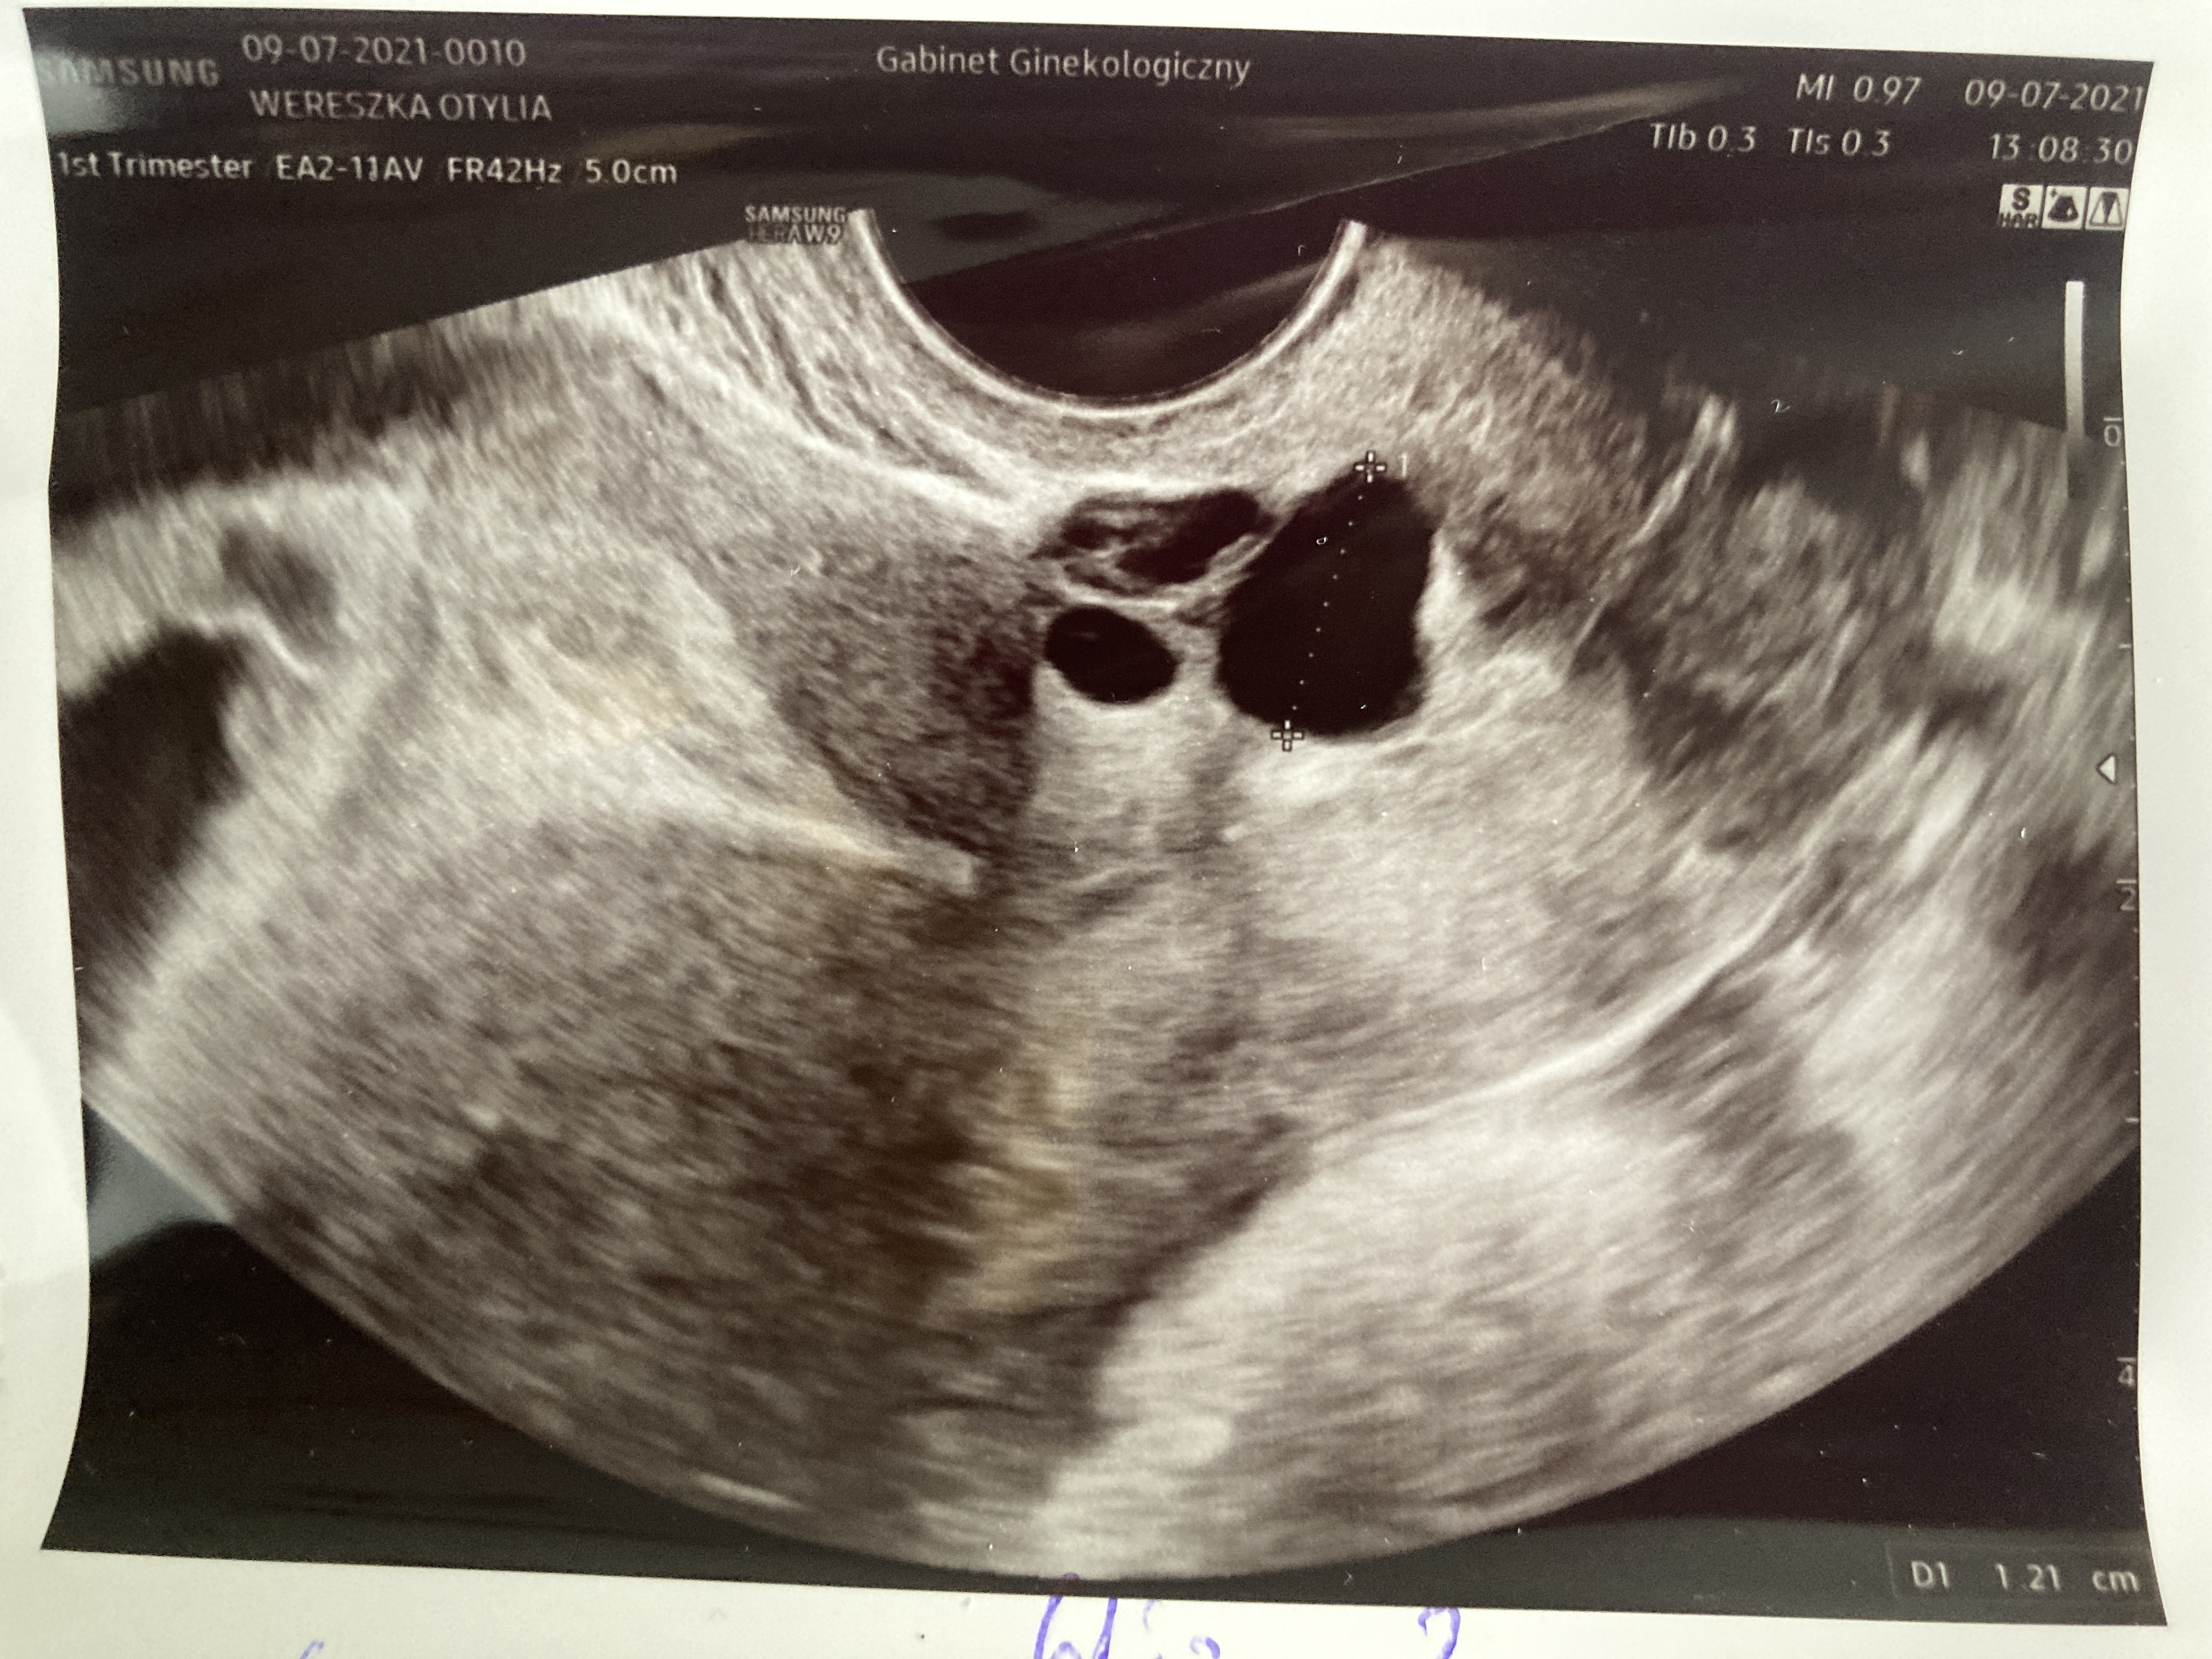

Dziewczyny coś nie daje mi spokoju. Ginekolog dała mi jeszcze takie zdjęcie i podpisała że torbiel. 5cm. Obok widać ciążowy z zarodkiem 4 cm. Czy to zniknie? Albo jest możliwość że coś jeszcze się pojawi?

Załączniki

• 18A6DD62-EF08-4C2E-977B-AB942652BE0D.jpeg

18A6DD62-EF08-4C2E-977B-AB942652BE0D.jpeg

2,5 MB · Wyświetleń: 124